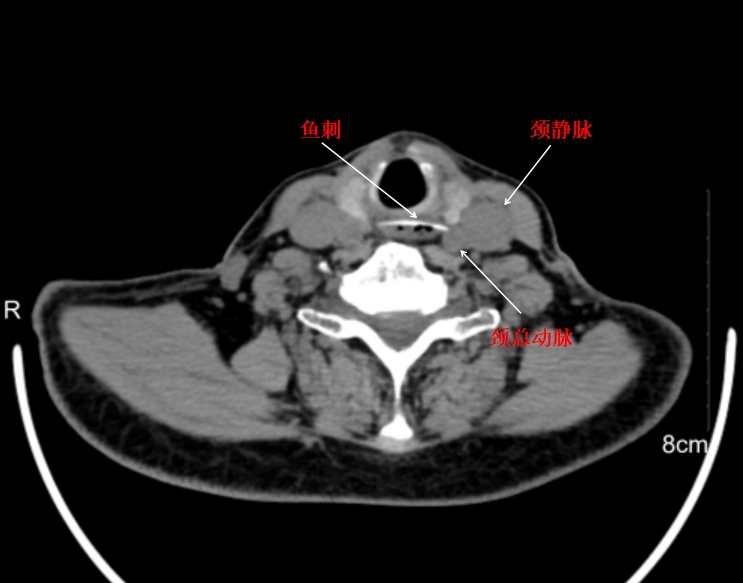

惊险!鱼刺紧贴颈总动脉

CT检查结果让经验丰富的许医生也捏了把汗:一根长达2.5厘米的鱼刺横梗在食管上段,尖锐的一端紧贴颈总动脉!这意味着每一次吞咽、每一次呼吸,鱼刺都可能刺破这根为大脑供血的重要血管,引发致命性大出血。

随即,老人被送往了内镜室。操作前,许医生深吸一口气,平稳地拿起胃镜。当内镜抵达食管上段时,显示屏上清晰地显示出那根致命凶器——鱼刺像一枚钉子深深扎入食管壁,距离颈动脉仅有毫厘之差。